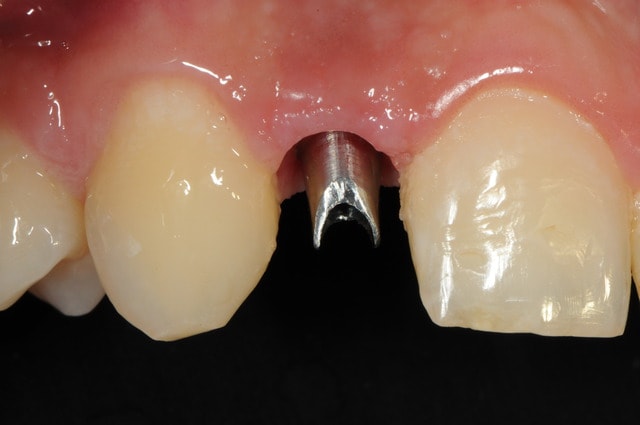

01/09/2010 à 16h54

-1 ou 2 mois plus tard ( je sais plus)

- empreinte avec transfert pop in

- pilier zircone esthétique Axiom

- prothèse et pilier

- pilier zircone en place

- couronne en place (petite compression gingivale)

fin du traitement